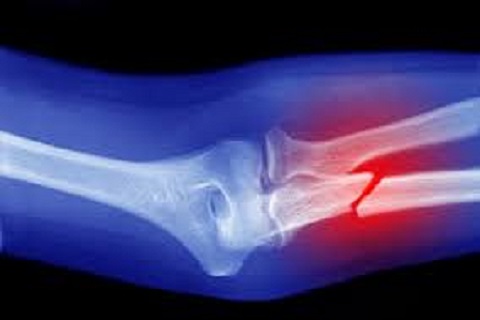

Luxaciones

Una luxación es la separación permanente de las dos partes de una articulación, es decir, se produce cuando se aplica una fuerza extrema sobre un ligamento, produciendo la separación de los extremos de dos huesos conectados.